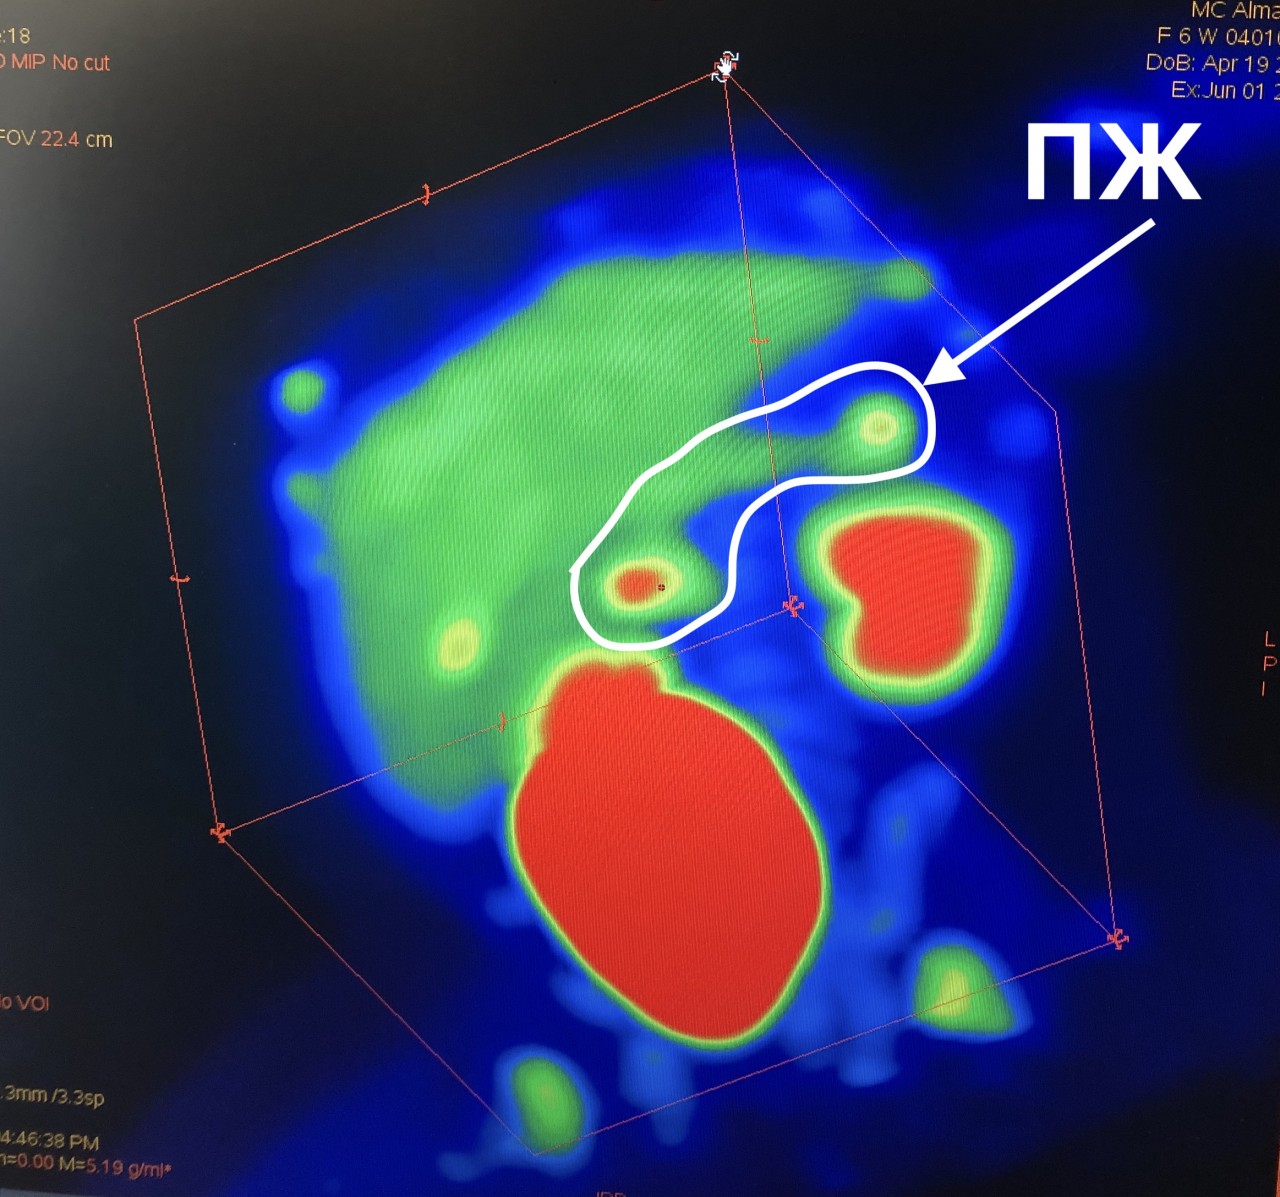

Фотографии медицинских исследований инсулиномы и синдрома Триады Уиппла